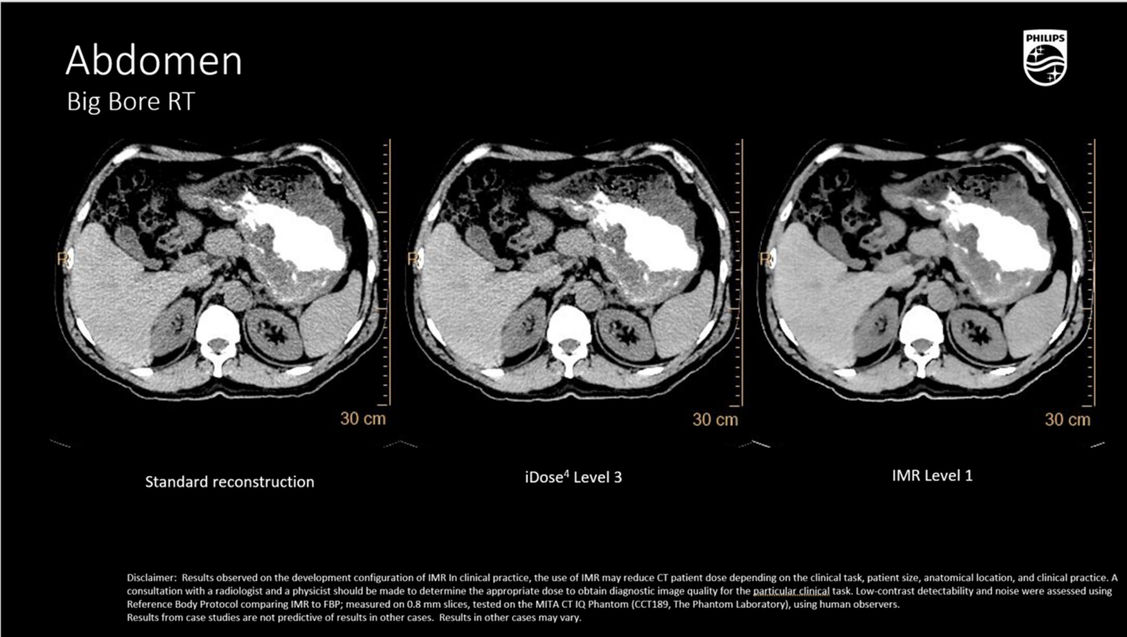

Технология Philips IMR позволяет одновременно снизить лучевую нагрузку на 60—80%, улучшить низкоконтрастное разрешение на 43—80% и снизить шум на 70—83%*. IMR дает уверенность в правильности показателей благодаря улучшенной визуализации мелких деталей